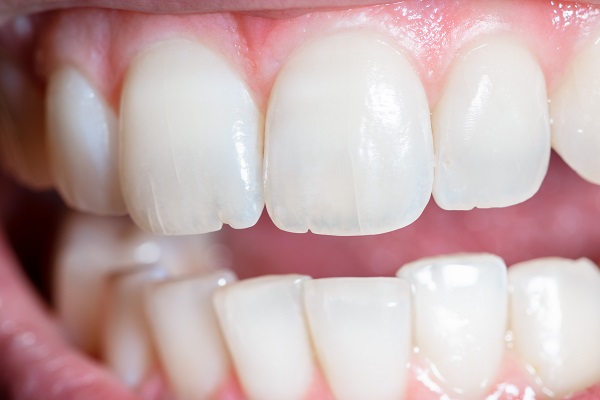

Treatment:

We’ll bond and splint the tooth to keep it stable.

If needed, we’ll do internal bleaching to restore the natural color.

Finally, we’ll place a custom crown so your tooth looks like nothing ever happened.